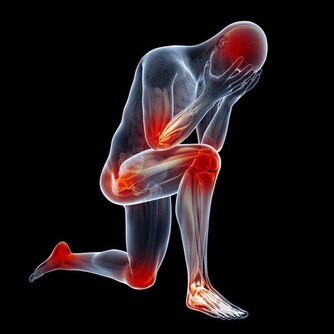

很多人飽受膝關節疼痛折磨甚至影響到日常生活。以下四種人需要重視這篇文章:關節嘎巴嘎巴響的人;腿疼的人;上下樓腿疼、膝蓋疼,有骨刺;O型腿的。

膝關節冷、上下樓梯疼、軟弱無力等,這都是常見的膝關節問題。

膝關節出問題,不管是什麼問題,都要給有效的刺激,才能康復。教您一個方法今天開始記住,膝關節乾澀的時候給膝關節「注潤滑液」!每天2~3分鐘,每天做下面這個運動,就是給膝關節注入潤滑液!膝蓋問題就能一次解決!

上樓疼、下樓疼、上下樓沒勁髕骨老化、膝關節炎症、髕骨軟化,積水、長骨刺、咔咔作響這種現象都會迅速好起來!